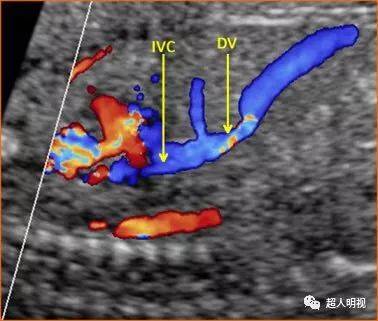

胎儿静脉导管血流

胎儿静脉导管血流,胎儿静脉导管血流频谱

孕早期超声扫查规范(fmf 版):静脉导管血流

胎儿静脉导管

胎儿静脉导管超声切面

胎儿静脉导管超声图片

静脉导管

静脉导管超声图